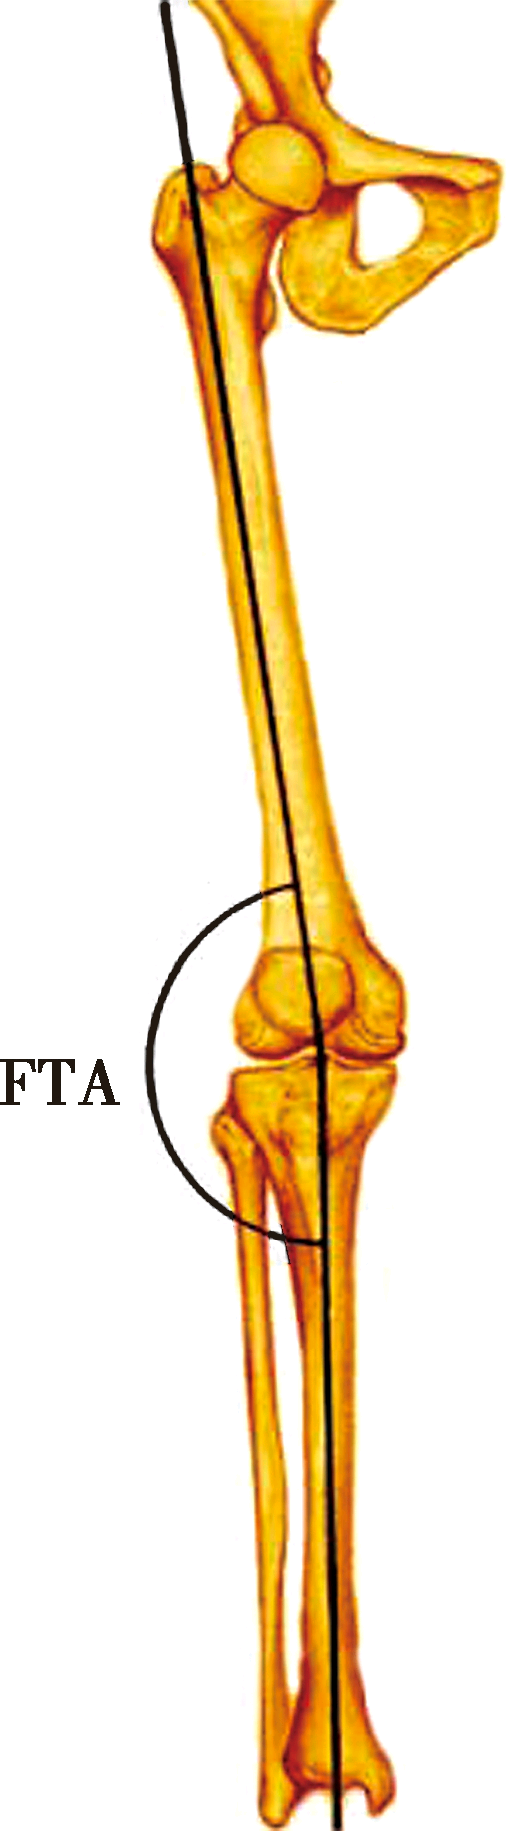

FTA:股骨解剖轴线与胫骨解剖轴线的夹角

胫股角(femoraltibial angle,FTA)是股骨解剖轴线与胫骨解剖轴线在膝关节中心相交形成的向外侧的夹角。此夹角平均为174°。